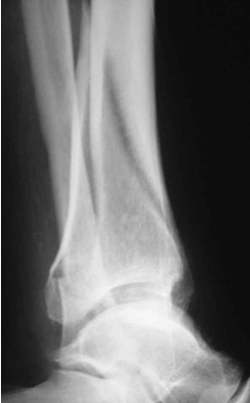

Distale Tibiafraktur mit Weichteilschaden

Die Fraktur reicht bis in das Sprunggelenk